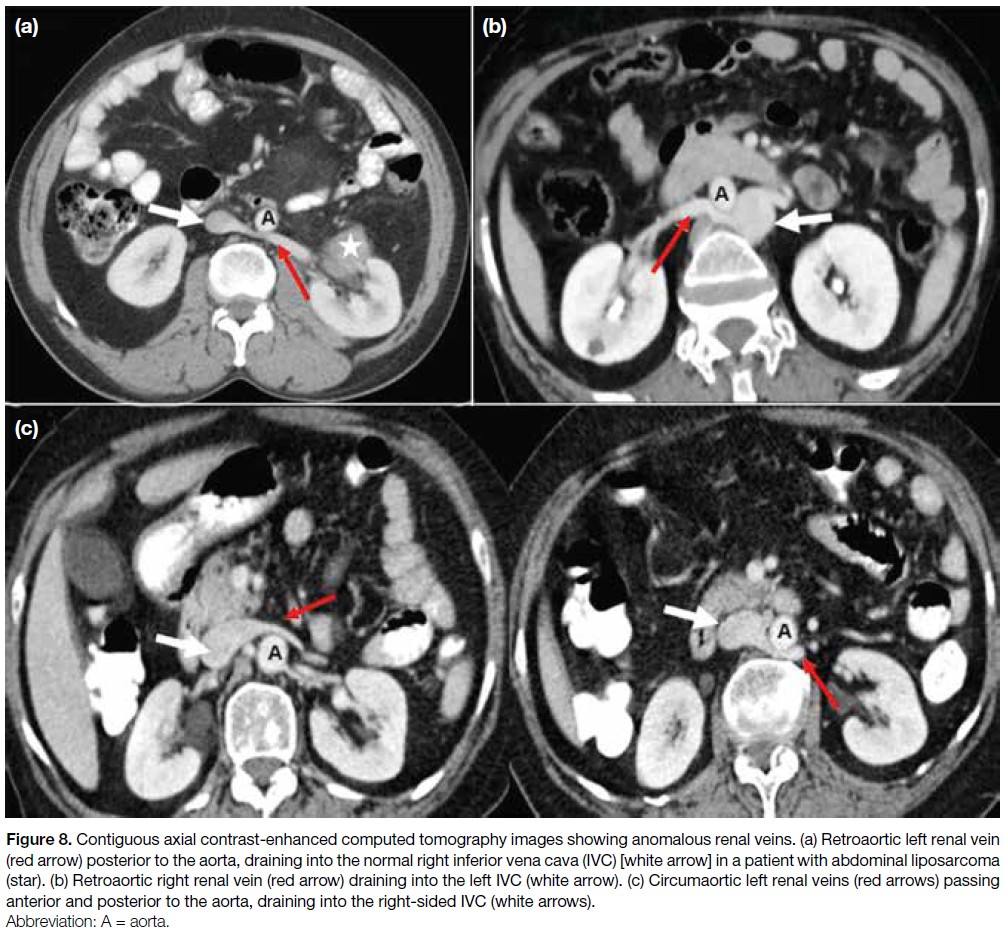

Figure 8. Contiguous axial contrast-enhanced computed tomography images showing anomalous renal veins. (a) Retroaortic left renal vein

(red arrow) posterior to the aorta, draining into the normal right inferior vena cava (IVC) [white arrow] in a patient with abdominal liposarcoma (star). (b) Retroaortic right renal vein (red arrow) draining into the left IVC (white arrow). (c) Circumaortic left renal veins (red arrows) passing anterior and posterior to the aorta, draining into the right-sided IVC (white arrows).